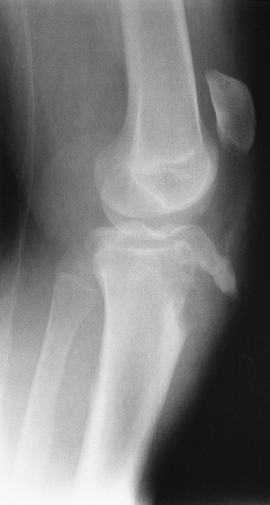

P.225

FIGURE 5-12 AP (A), lateral (B), and stress views (C) of a Salter-Harris III femoral fracture.